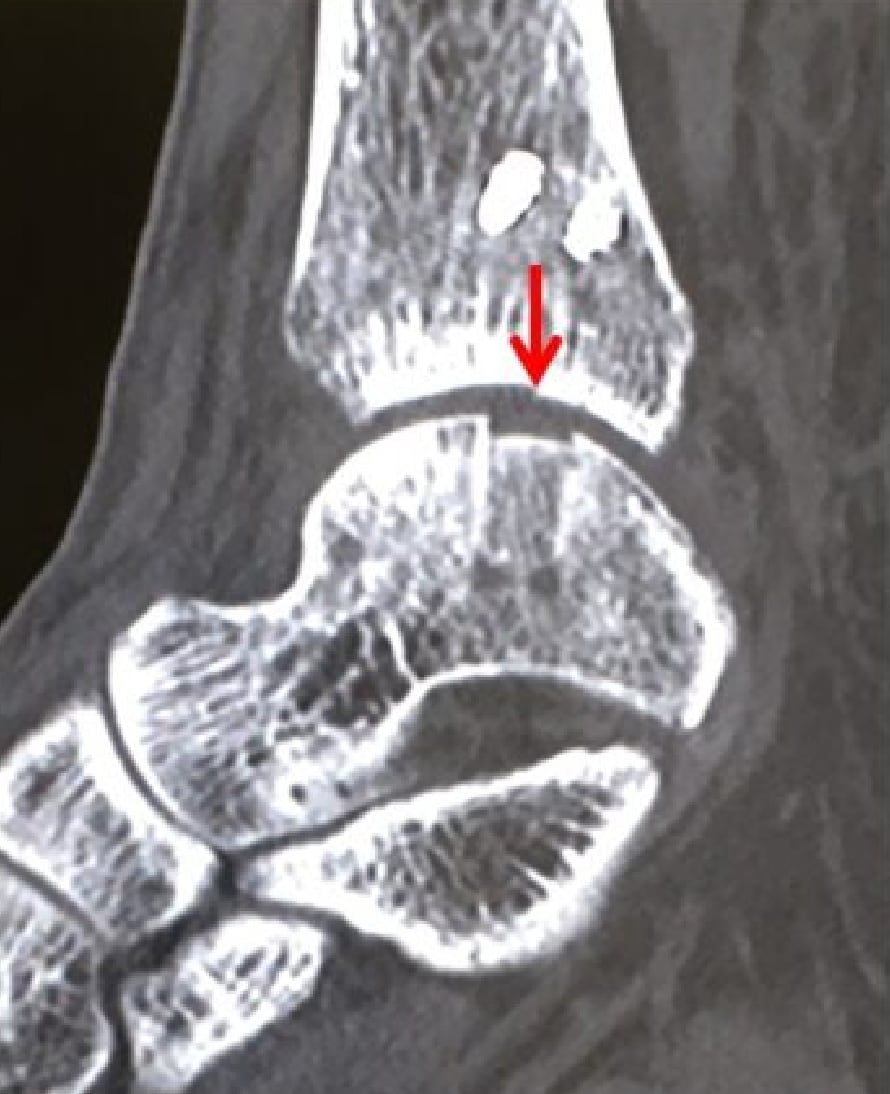

2020-12-09 スポーツ整形 ページ内リンク 距骨骨軟骨損傷(離断性骨軟骨炎)【スポーツ整形外科】 距骨骨軟骨損傷(離断性骨軟骨炎)【スポーツ整形外科】 軟骨とその下の骨が剥がれてきて痛みが出る。⇒骨穿孔/骨軟骨片固定/骨軟骨柱移植 患部の状態により最適な治療方法を選択します。 骨軟骨柱移植前 骨軟骨柱移植後 骨軟骨柱移植術後CT 関連ページ スポーツ整形 一覧へ戻る